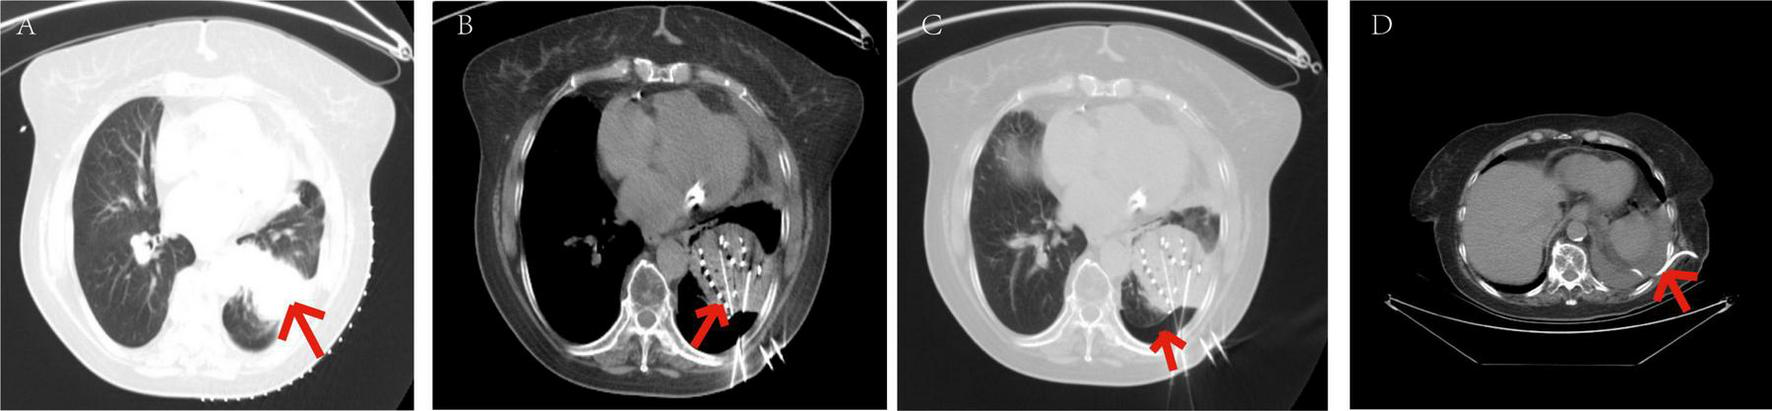

moderate and severe pneumothorax were 13 cases (36.11%) and 9 cases (25%), respectively. Patients with mild pneumothorax did not receive any specific treatment, as shown in Figure 8. Among the 13 patients with moderate pneumothorax, 6 received conservative treatment, and 4 showed improvement postoperatively, transitioning to mild pneumothorax. Patients with moderate and severe pneumothorax (7 and 9 cases, respectively) had their symptoms relieved through closed chest tube drainage, with symptoms resolving within a maximum of 6 days, as shown in Figure 9.

FIGURE 8

Patients with mild pneumothorax did not receive any specific treatment. The patient, an elderly female, diagnosed with adenocarcinoma of the left lower lobe of the lung. Under our department’s care, underwent CT-guided percutaneous 125I particle implantation close-range radiotherapy. (Indicated by the red arrow) (a) preoperative CT lung window showing a lesion measuring 5.6 × 6.2 cm. (b) Immediate postoperative CT reexamination showing mild pneumothorax formation in the lung window. (c) Intraoperative CT lung window showing pulmonary emphysema adjacent to the lesion in the left lower lobe and cavities visible within the lesion. (d) Intraoperative mediastinal window showing the implantation of 91 particles in the lesion of the left lower lobe. The patient’s mild pneumothorax was self-absorbed, and on reexamination 2 days later, the pneumothorax had completely disappeared.